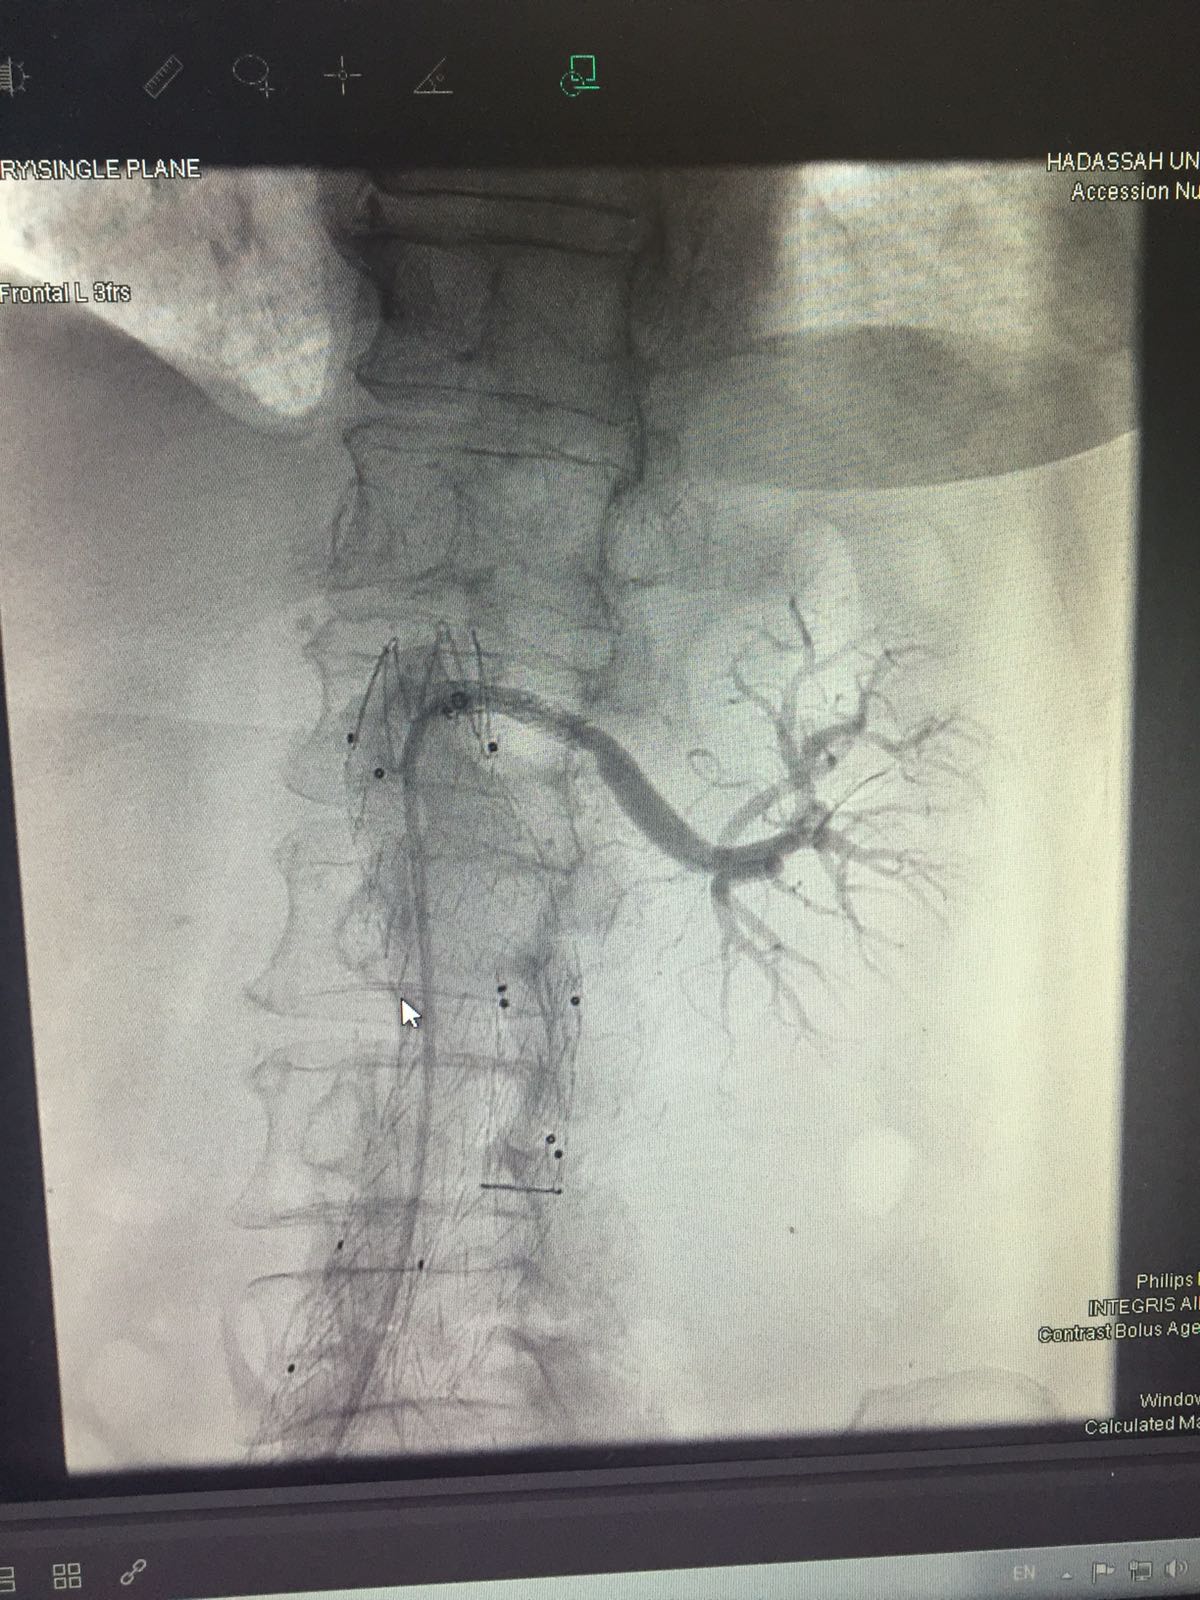

לפני כשנתיים הגיעה אסתר רפאל (68) לביקורת בבית החולים 'קפלן', בעקבות ניתוח שעברה בעברה. הביקורת העלתה שהיא סובלת מלחץ דם גבוה והיא נתבקשה להיות במעקב. מספר ימים לאחר מכן לחץ הדם החל להשתולל, היא אושפזה, עברה בדיקות ושוחררה עם המלצה לפנות לרופא מומחה בתחום רפואת הכליות. "הגעתי לבית החולים הדסה לדוקטור אירית מור-יוסף, רופאה מקסימה, שהפנתה אותי לביצוע בדיקות מקיפות. אחרי שהגיעו התוצאות זימנו אותי באופן מידי לבצע צנתור, בשל חסימה של שני העורקים המובילים אל הכליות" מספרת אסתר. לדבריה עד לאותו רגע היא לא הרגישה שמשהו חריג מתחולל בגופה. "הרגשתי טוב מאוד" היא אומרת "לא כאב לי כלום, תפקדתי כרגיל ויכול מאוד להיות שאם לא הייתי מגיעה לביקורת על משהו אחר בכלל, הייתי מגלה את הבעיה בכליות בשלבים מאוד מאוחרים".

זמן קצר לאחר מכן הוכנסה רפאל לחדר ניתוח, להליך צנתור שהיה אמור להימשך כ-40 דקות. "בפועל הניתוח הסתבך ונמשך שש שעות. היה שם דימום והזעיקו את כל הרופאים ולמעשה הצילו את חיי" מספרת אסתר.

הניתוח הצליח והיא שבה לשגרת חיים רגילה, שנמשכה כחצי שנה, עד שלילה אחד התעוררה משנתה בשל כאבים במותן שמאל. "אני לא טיפוס שנלחץ, אבל בגלל ההיסטוריה שלי חשבתי שצריך להתייעץ עם הרופאה שמלווה אותי. כשתיארתי לה את הכאב היא ביקשה שלהגיע מידית לבית החולים". אסתר הגיעה לבית החולים ושם התבשרה שיש צורך לצנתר שוב, היא הוכנסה לחדר ניתוח אך במהלך ההליך התברר שהוא בלתי אפשרי לביצוע. "בצנתור הקדמה הצליחו להחזיר לפעילות רק את כליה שמאל, אז למעשה הייתי עם כליה אחת שתפקדה. הפעם נאמר לי שהתיישב קריש דש על העורק של הכליה המתפקדת ולכן לא ניתן היה לצנתר אותה". באותו מעמד קיבלה רפאל גם בשורה נוספת, היא תצטרך לעבור טיפולי דיאליזה עד סוף חייה. "הייתי המומה, אני יודעת שמדובר בטיפולים לא פשוטים וכמעט יומיומיים ולא ידעתי איך אני אעמוד בזה. התחלתי טיפולי דיאליזה בהדסה ואז פנה אליי הפרופסור שביצע את הצנתור בפעם הראשונה והציע לנסות שוב. חששתי, אבל הסכמתי ואמרתי לו שאני סומכת עליו. העדפתי לעבור את זה שוב, למרות הסיכון שכרוך בכך, ולא להישאר עם דיאליזה לכל החיים". הרופאים הצליחו אומנם להמיס את קריש הדם, אבל אסתר עדיין הייתה זקוקה לטיפולי דיאליזה. היא החלה להגיע ל'הדסה' לצורך הטיפולים עד שהציעו לה לעבור לבית החולים החדש 'אסותא' באשדוד. "הם אמרו לי שאני אצטרך לבצע את זה כמעט כל יום ולכן חבל שאסע בכל יום לירושלים, כשיש בית חולים קרוב לבית". רפאל גם קיבלה שיחת טלפון מפרופסור עדי לייבה, מנהל מכון נפרולוגיה ויתר לחץ דם 'באסותא', שהרגיע אותה באופן אישי והבטיח לה שהיא בידיים הכי טובות שאפשר. היא הגיעה לבית החולים על מנת לעבור את ההליך, עברה בדיקות מקיפות שהראו שתפקודי הכליה טובים מעבר למצופה ולכן הוחלט להשהות את הדיאליזה. "שבוע ימים הגעתי לבית החולים יום-יום והייתי תחת מעקב של כל המומחים במחלקה. כולם סיכמו פה אחד שכרגע אין יותר צורך בדיאליזה. את הבשורה קיבלתי בדיוק ביום ההולדת שלי, זאת הייתה המתנה הכי טובה שיכולתי לבקש. בעלי אמר שיש לנו סיבה נהדרת לחגוג ויצאנו לאכול במסעדה. עכשיו אני נמצאת במעקב צמוד במחלקה, בתקווה שנפרדתי מהדיאליזה לנצח. מעולם לא דמיינתי שביקור שלי 'באסותא' יסתיים בבשורה מפתיעה ומדהימה כל כך. זאת מחלקה מדהימה עם פרופסור לייבה המקסים והאנושי וצוות מקצועי ומסור. זאת הזדמנות נהדרת להודות לכולם".

"אוטם, כלומר, חסימה של העורקים המובילים לכליות. זה נושא שאנחנו פחות שומעים עליו, אבל כמו שיש אוטם שריר הלב שמוביל להתקף לב או אוטם העורק שמוביל למוח, שגורם לשבץ. כך ברגע שיש חסימה של עורקים המובילים לכליות הן מפסיקות לתפקד. החסימה היא לא מידית וזה בדרך כלל מתחיל באיזושהי היצרות שהולכת וגדלה וכך אחד העורקים או שניהם נחסמים. שמנו לב שיכול להיווצר מצב שהעורק נסתם והחולה מגיע לדיאליזה, אפשר להוציא אותו ממנה. להבדיל מעורקים אחרים סביב הכליה יכולים להיווצר מעקפים והיא מצליחה לשרוד. בנוסף לא הרבה יודעים שאפשר לפתוח את העורקים הללו".

מה קרה במקרה של אסתר?

"כשאסתר הגיעה להדסה בהתקף היא למעשה חוותה חסימה מלאה של שני העורקים. זה משהו שקורה בהדרגה ולפעמים בצורה שקטה ואז יש אירוע פתאומי של סתימה סופית. בהדסה הצליח פרופסור בלום לפתוח ולהציל כליה אחת, אבל זה לא היה מספיק והיא החלה טיפולי דיאליזה. בטיפול כזה בן אדם מגיע 3 פעמים בשבוע לבית החולים ומתחבר ל-4 שעות למכונה שמחליפה את תפקוד הכליות. לאחר מכן היא הופנתה אלינו, כשהיתרון כאן שיש מומחה כליות שראה אותה בכל יום. בפעם הראשונה היא הגיעה כבר במטרה לעשות דיאליזה, אבל ראינו אותה ובהתאם לתוצאות הבדיקות החלטנו לא לעשות. אנחנו הראנו שהפתיחה שנעשה לה בזכות הסעיפים העוקפים, איפשרה מצב של הפסקת הדיאליזה, תוך מעקב צמוד. זה משהו מהפכני, שכן נהוג לחשוב שמי שעובר התקף כליה ונזקק לדיאליזה יזדקק לה כל חייו. לאסתר יש עדיין אי ספיקת כליות מסוימת ולכן היא נמצאת במעקב ואנחנו כל הזמן עם האצבע על הדופק. אם חלילה ההיצרות תתקדם, נוכל לצנתר שוב. אם החולה נמצא במחלקה שעוקבת אחריו ויכולה לתת לו מענה מלא של מיטב המומחים מכל התחומים, הוא יכול בראש שקט לחזור לחיים רגילים".